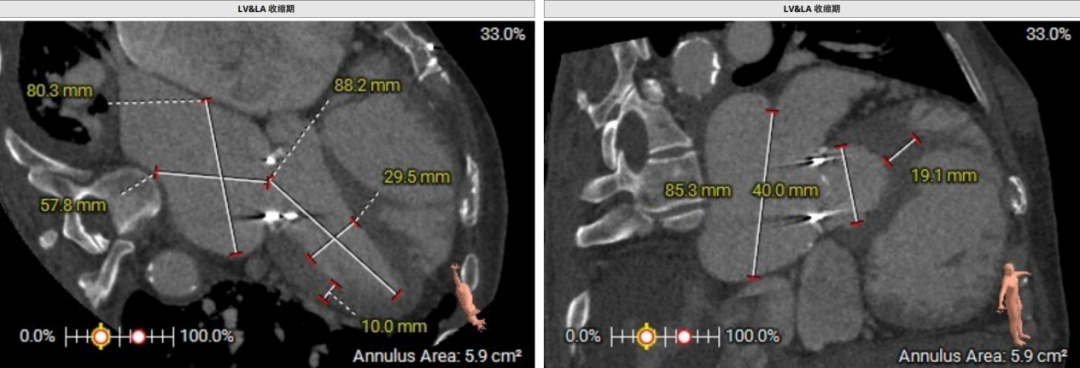

术前CT评估示:患者二尖瓣生物瓣置换术后,原生物瓣型号未知,生物瓣金属环平均内径25.9mm,外径31.5mm,瓣架高度15.9mm;

模拟27mm瓣膜植入情况: